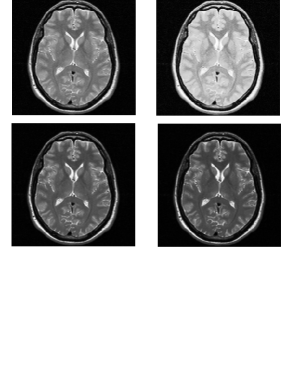

3.1.2. Adding known levels of non-standardness

We combine eight different ranges of the slopes and to introduce small, medium, and large scale non-standardness into the scenes. This means that, for each clean scene, we obtain eight scenes, one of which is the default clean scene itself, two scenes consisting of small scale non-standardness, two scenes consisting of medium scale non-standardness, and three scenes consisting of large scale non-standardness. The ranges of applied non-standardness are given in Table 1. We have arrived at these values by examining the training part of the standardization process through computing the ranges of the slopes and that are utilized in standardizing the corrected scenes. Figures 4 and 5 illustrate the process of introducing known levels of non-standardness into the clean slices of a PD and a T2-weighted scene utilized in our study. In both figures, the first display shows the original clean slice and the rest show the resulting non-standard slices.

![]() |